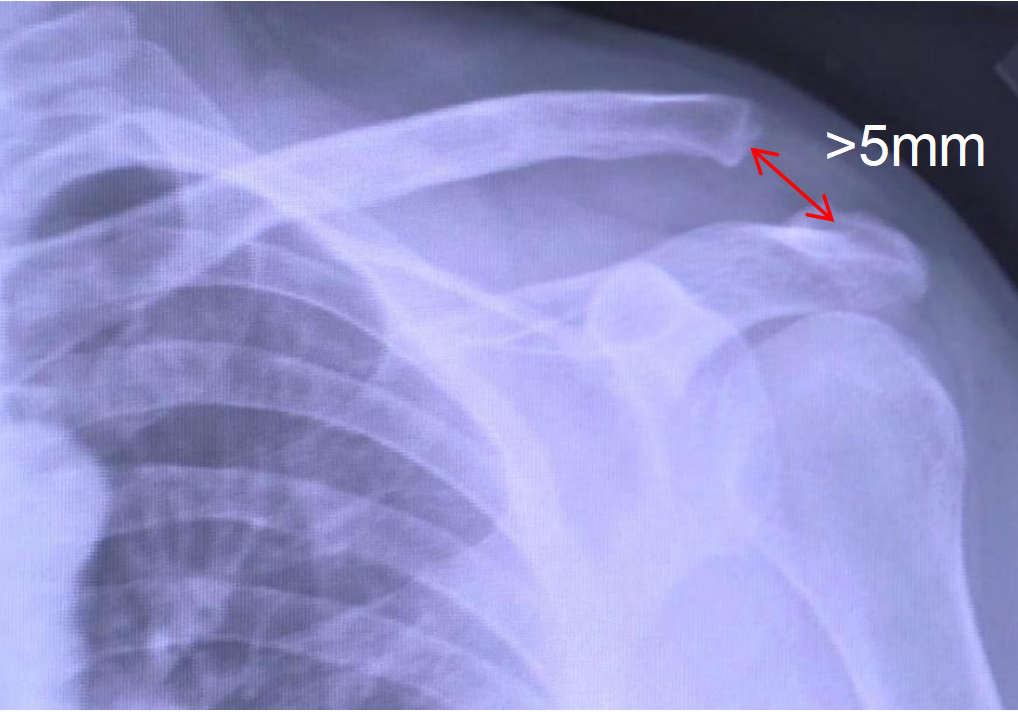

影像(xiang)學表(biao)現

鎖(suo)骨上(shang)翹,肩(jian)鎖(suo)關節間(jian)隙大于5mm